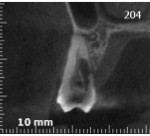

Allora per capirci qualcosa in più ho fatto una cone beam.

“possibile però che un difetto perfettamente identificabile e raggiungibile con microsopio o anche solo con occhialini ingrandenti, sia qualcosa di fronte al quale arrendersi?”

Del resto Heithersay operava negli anni antecedenti al 1999, quando ingrandimenti e microscopio non erano così diffusi e nemmeno l’utilizzo di scansioni tridimensionali dei denti. E se leggi l’articolo in cui descrive la tecnica che utilizzava vedrai che rabbrividirai. Con quella tecnica antidiluviana mi stupisco che abbia avuto un successo così alto!

Come potrai vedere in questo video, il mio pensiero non faceva una piega. Con microsopio e cone beam operare casi del genere è una cosa è perfettamente fattibile e, ti dirò, non è nemmeno difficile.